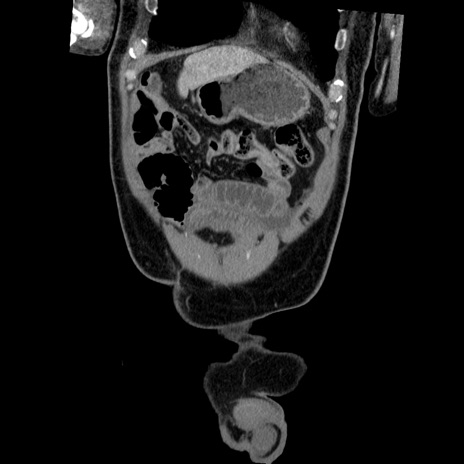

横断像

【症例】50歳代男性

【主訴】腹痛

【現病歴】AVMからの被殻出血のため回復期リハ病棟入院中。 本日午後3時頃急に下腹部痛が出現した。

【既往歴】AVM、被殻出血、虫垂炎、高血圧

【身体所見】意識晴明、左半身不全麻痺、会話の理解は良好、36.5°C、腹部:膨隆、全体に板状硬、下腹部正中に圧痛点あり、反跳痛-、筋性防御不明、右下腹部にope scar

【データ】WBC 9400、CRP 0.06